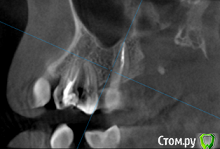

St. Опубликовано 26 августа, 2016 Поделиться Опубликовано 26 августа, 2016 Все три пролечены не очень хорошо, в идеале перелечить и сделать на них коронки. Но на сладкое ни один из них не может реагировать. Возможно реагирует 7 или 3, у которых оголена часть корней за счет вашего парадонтита. 1 Ссылка на комментарий

Гарриевич Опубликовано 27 августа, 2016 Поделиться Опубликовано 27 августа, 2016 возможно пропущенный канал, а возможно Вам "кажется" и реагируют все таки живые зубы. В любом случае данный снимок показывает не очень качественное лечение, но это только снимок 1 Ссылка на комментарий

татьяна tat Опубликовано 27 августа, 2016 Автор Поделиться Опубликовано 27 августа, 2016 возможно пропущенный канал, а возможно Вам "кажется" и реагируют все таки живые зубы. В любом случае данный снимок показывает не очень качественное лечение, но это только снимок Ссылка на комментарий

St. Опубликовано 27 августа, 2016 Поделиться Опубликовано 27 августа, 2016 Если кажется, что больше всего беспокоит 5, с него и начните. Но в будущем лучше перелечить все. 1 Ссылка на комментарий

Beznika Опубликовано 8 сентября, 2016 Поделиться Опубликовано 8 сентября, 2016 на 5 ке материал вывели за апекс. резекцию возможно придётся делать верхушки корня... + карман у вас есть за 6кой. а так всё равно перелечивать надо... масса пористая в каналах и не гомогенная. (не однородная) Ссылка на комментарий